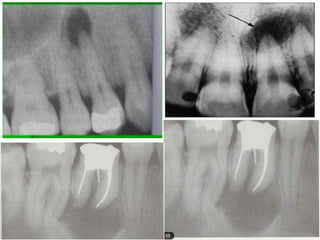

• Radiographically the tooth show widening of

PDL space, in some patient the tooth may

show discontinuity in laminadura

• Widening of PDL space

• Discontinuity in lamina dura

• Thickening of lamina dura

• Condensing osteitis

• Large open cavity with direct access to the

pulp chamber,

• Discontinuity of lamina dura

• Widening of lamina dura

• Radiographically thetooth show widening of PDL space, in some patient the tooth may show discontinuity in laminadura

• Widening ofPDL space • Discontinuity in lamina dura • Thickening of lamina dura • Condensing osteitis

• Large opencavity with direct access to the pulp chamber, • Widening of pdl space • Discontinuity of lamina dura • Widening of lamina dura